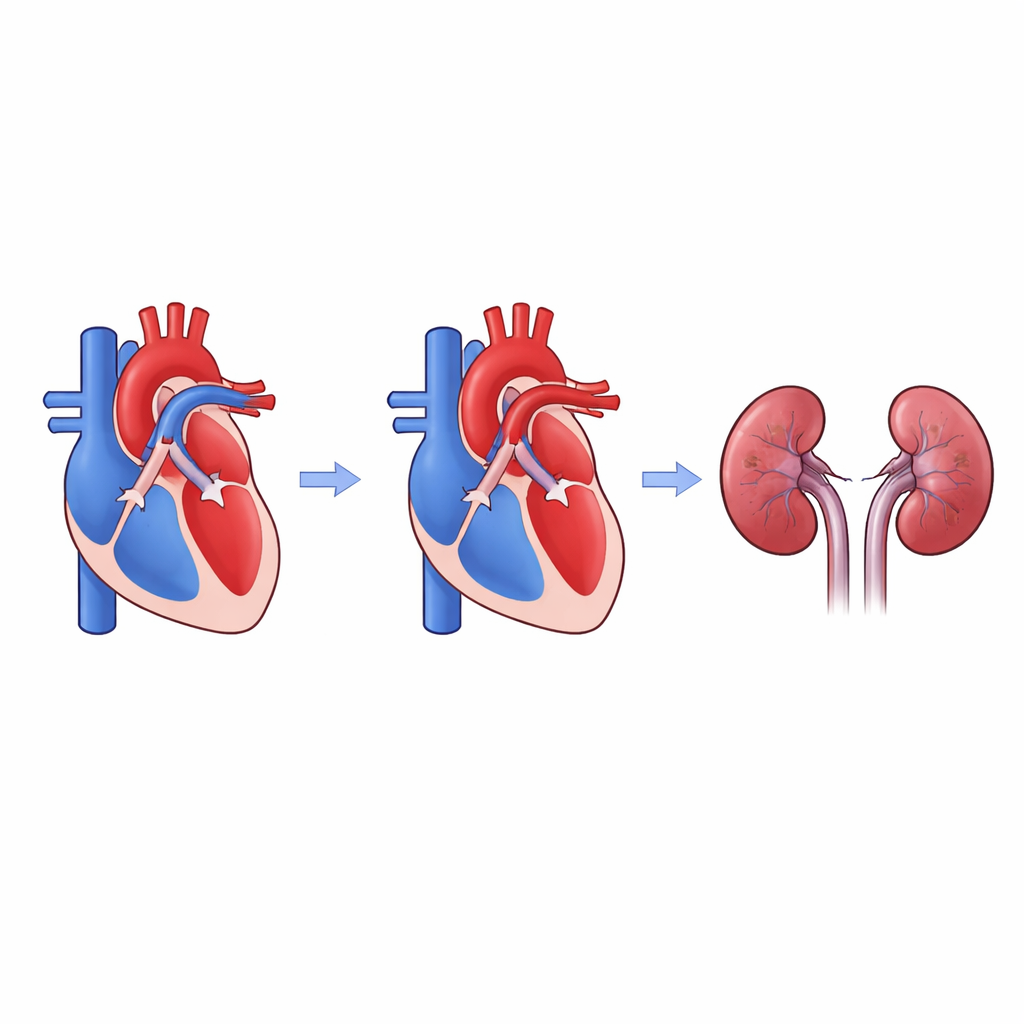

Prima della nascita, i bambini hanno un breve vaso sanguigno chiamato dotto arterioso che aiuta a bypassare i polmoni. Dopo la nascita dovrebbe chiudersi. Nei neonati molto prematuri, tuttavia, spesso rimane aperto; i medici lo chiamano dotto arterioso pervio, o DAP. Quando il DAP è ampio e influisce fortemente sul flusso sanguigno, può sottrarre sangue al corpo e ai reni e convogliare troppo verso i polmoni. Allo stesso tempo, molti ospedali hanno adottato un approccio più conservativo di osservazione anziché chiudere subito i DAP con farmaci. Questo significa che alcuni neonati fragili possono convivere con questo vaso cardiaco aggiuntivo per mesi, sollevando il timore che i loro reni possano subirne le conseguenze nel tempo.

Il team ha rivisto le cartelle cliniche di una singola unità di terapia intensiva per 216 neonati nati prima delle 29 settimane di gestazione che necessitavano ancora di supporto respiratorio alla quarta settimana di vita. A questi bambini venivano eseguite ecografie cardiache di routine da circa quattro settimane di vita fino alla dimissione, permettendo ai medici di vedere se il DAP era ancora aperto e se era sufficientemente grande da influenzare fortemente il flusso. I ricercatori hanno raggruppato i neonati in base alla durata dell’esposizione a un DAP fortemente influente: circa uno-due mesi, due-tre mesi, o tre mesi o più. Hanno poi monitorato chi sviluppava una «lesione renale acuta tardiva»—un nuovo danno renale a partire da quattro settimane di vita o oltre—osservando gli aumenti della creatinina sierica, un marcatore standard della funzione renale.

Complessivamente, il 18 percento di questi neonati estremamente prematuri ha sviluppato una lesione renale tardiva, e la maggior parte di quei casi era grave. A prima vista, i neonati il cui DAP è rimasto fortemente aperto per almeno 12 settimane sembravano avere circa quattro volte le probabilità di lesione renale grave rispetto ai neonati senza tale lunga esposizione. Ma quegli stessi bambini erano anche i più prematuri e i più piccoli alla nascita—fattori già noti per aumentare il rischio renale. Quando i ricercatori hanno aggiustato i dati in base all’epoca gestazionale alla nascita, il presunto rischio aggiuntivo dovuto a un DAP di lunga durata non è risultato più statisticamente significativo. Durate più brevi di esposizione al DAP non hanno mostrato un aumento significativo dei problemi renali. In altre parole, la prematurità stessa, insieme ad altre malattie, potrebbe spiegare gran parte del rischio.